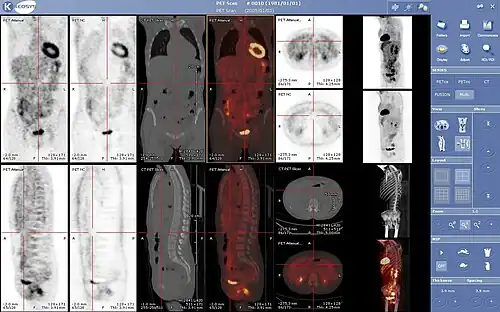

Hybrid scanning techniques

In some centers, the nuclear medicine scans can be superimposed, using software or hybrid cameras, on images from modalities such as CT or MRI to highlight the part of the body in which the radiopharmaceutical is concentrated. This practice is often referred to as image fusion or co-registration, for example SPECT/CT and PET/CT. The fusion imaging technique in nuclear medicine provides information about the anatomy and function, which would otherwise be unavailable or would require a more invasive procedure or surgery.

More recent developments in nuclear medicine include the invention of the first positron emission tomography scanner (PET). The concept of emission and transmission tomography, later developed into single photon emission computed tomography (SPECT), was introduced by David E. Kuhl and Roy Edwards in the late 1950s. Their work led to the design and construction of several tomographic instruments at the University of Pennsylvania. Tomographic imaging techniques were further developed at the Washington University School of Medicine. These innovations led to fusion imaging with SPECT and CT by Bruce Hasegawa from University of California, San Francisco (UCSF), and the first PET/CT prototype by D. W. Townsend from University of Pittsburgh in 1998.

PET and PET/CT imaging experienced slower growth in its early years owing to the cost of the modality and the requirement for an on-site or nearby cyclotron. However, an administrative decision to approve medical reimbursement of limited PET and PET/CT applications in oncology has led to phenomenal growth and widespread acceptance over the last few years, which also was facilitated by establishing 18F-labelled tracers for standard procedures, allowing work at non-cyclotron-equipped sites. PET/CT imaging is now an integral part of oncology for diagnosis, staging and treatment monitoring. A fully integrated MRI/PET scanner is on the market from early 2011.